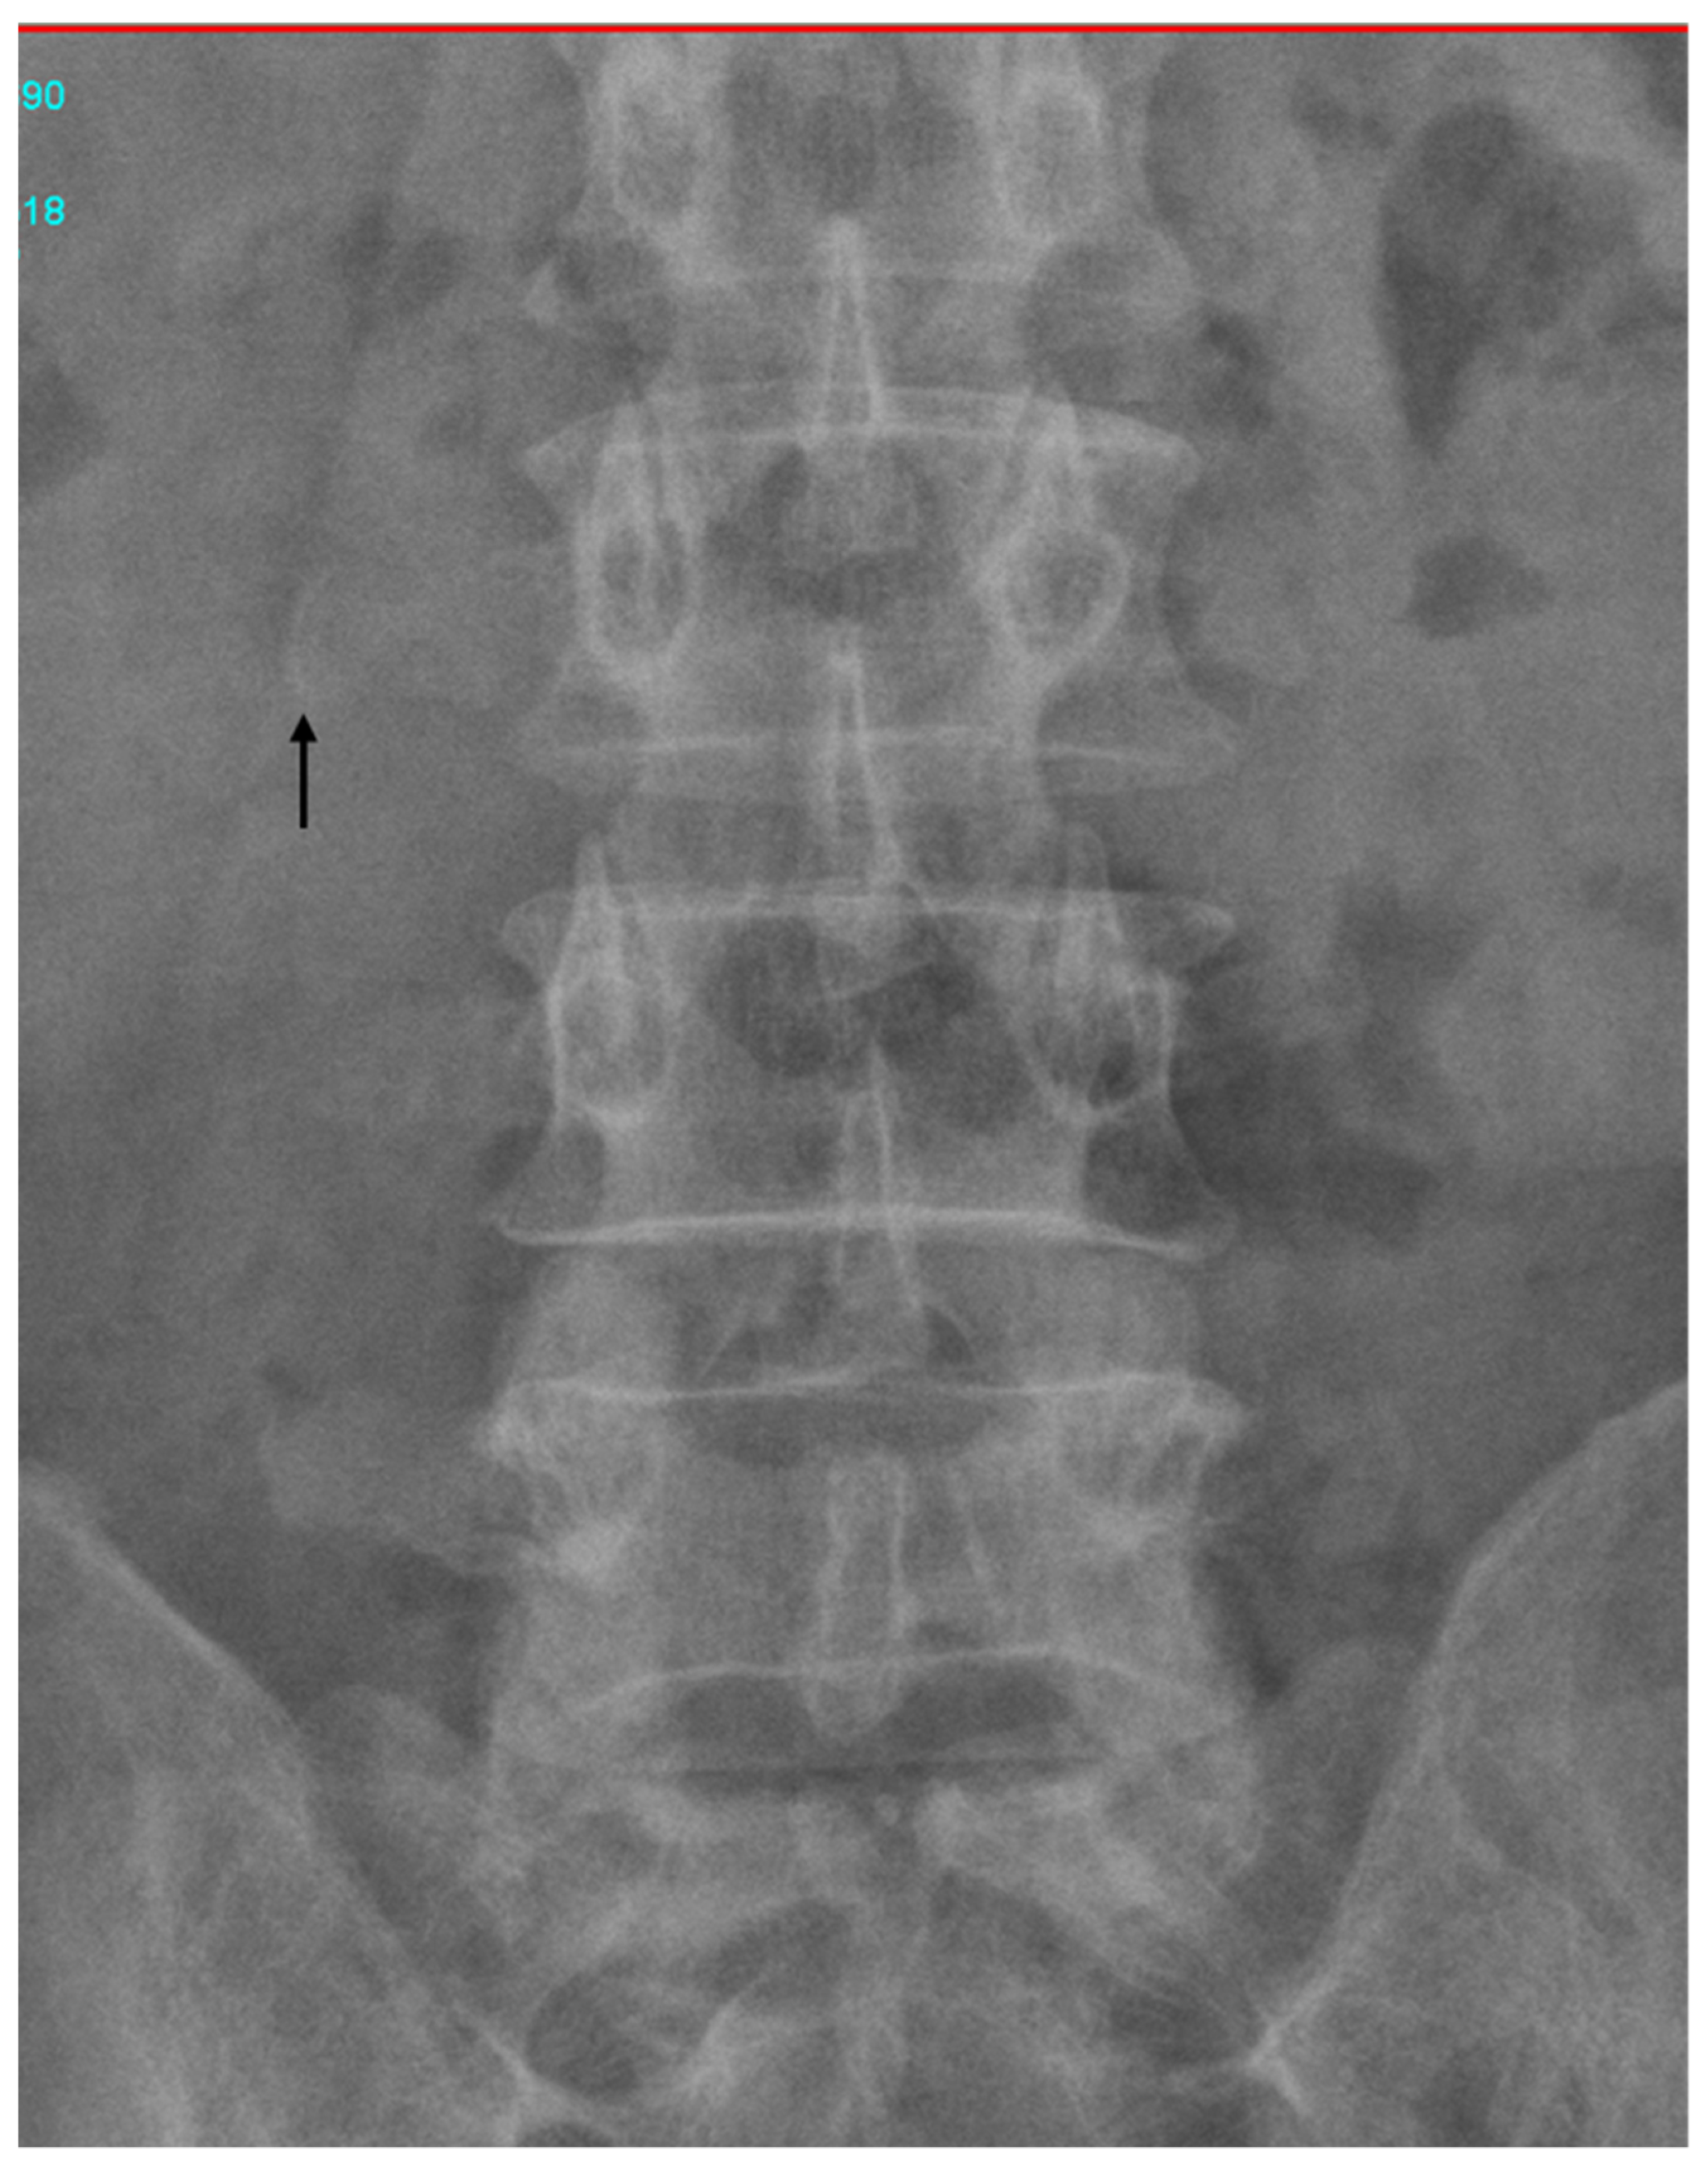

Figure 3. Abdominal radiographs, which revealed that the needle was on the right side of the third lumbar spine vertebra. The symptoms and signs of a retained surgical item include adhesion, foreign body migration, visceral perforation, and abscess formation [1]. These symptoms can occur early in the postoperative period or may develop after months or years [5]. In prior instances, retained surgical suture needles were surgically removed. However, our patient developed symptoms and signs of a retained needle 28 years after his surgery, by which point the needle had migrated to the ampulla of vater, from where it was easily removed through ERCP. Migrated surgical clips, stents, gauze pieces, suture materials, and fragments of t-tubes have all been reported as retained iatrogenic foreign bodies causing CBD obstruction and subsequent sequelae [2]. To our knowledge, this is the first reported case in which a retained surgical needle migrated to the ampulla of vater. Needles comprise 0.06–0.11% of foreign bodies that are retained during surgery [7]. Preventing instances of unintentionally retained surgical materials is a critical problem. A nationwide Brazilian study of retained surgical foreign bodies reported that challenging medical situations, security protocol omission, and inadequate work conditions contributed to retained foreign bodies. Sponges are notoriously overlooked because they are routinely inserted into cavities to expose the operative field. Thus, a preventive protocol could involve the introduction of the use of sponge-holding forceps [8]. In conclusion, CBD obstruction caused by foreign bodies can be safely ameliorated through ERCP without complications noted during follow-up.